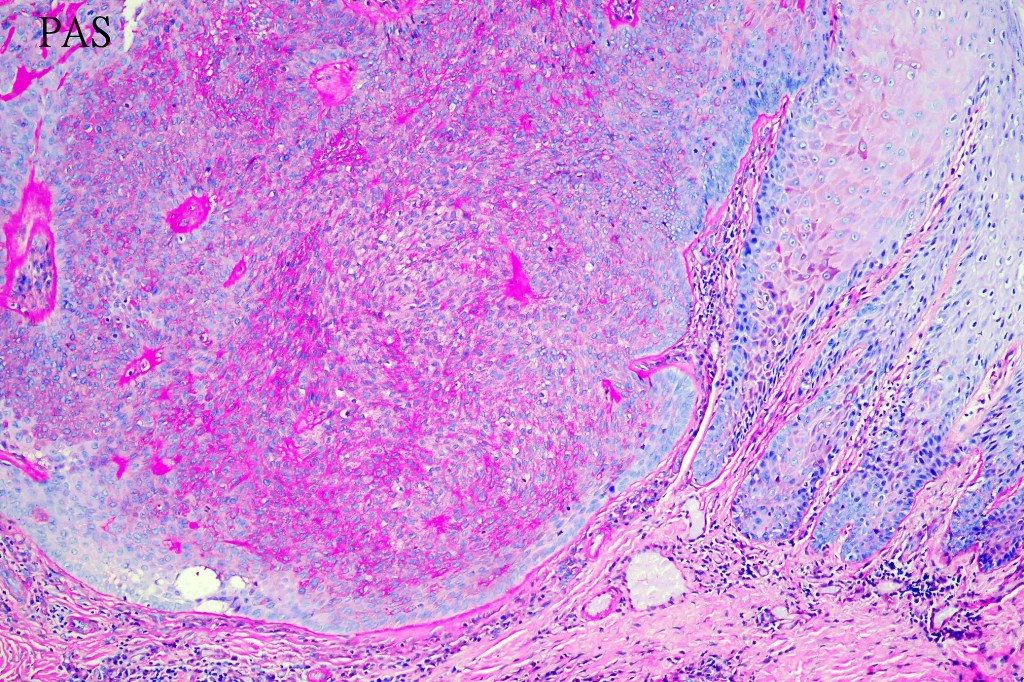

Histologicla features

•Multilobular growth connecting with epidermis & sometimes adjacent follicular external root sheath

•Small epithelial cells with often vacuolated cytoplasm and showing peripheral palisading

•Small nucleoli with vesicular nucleoli

•Rare or no mitoses

•No pleomorphism

•Eosinophilic thick basement membrane

•Overlying hyper- & parakeratosis

•Variable trichilemmal keratinization

•PAS +ve cytoplasm